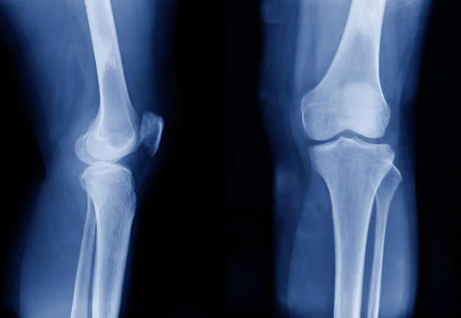

무릎 관절 통증의 원인

무릎 관절 통증의 원인은 다양합니다. 다음은 대표적인 원인들입니다.

- 퇴행성 관절염: 나이가 들면서 무릎 관절의 연골이 마모되어 발생하는 질환입니다. 통증과 함께 부종이 동반될 수 있으며, 움직임이 제한됩니다.

- 외상: 스포츠 활동이나 사고로 인한 외상은 무릎의 인대나 연골에 손상을 줄 수 있습니다. 이로 인해 급작스러운 통증 및 부기가 발생할 수 있습니다.

- 염증성 질환: 류마티스 관절염과 같은 염증성 질환은 면역 시스템에 문제가 생겨 무릎 관절의 염증과 통증을 유발합니다.

- 과사용: 무리한 운동이나 반복적인 동작은 무릎 관절에 과도한 스트레스를 주어 통증을 유발할 수 있습니다. 특히, 달리기나 점프가 많은 운동을 하는 경우 위험이 증가합니다.